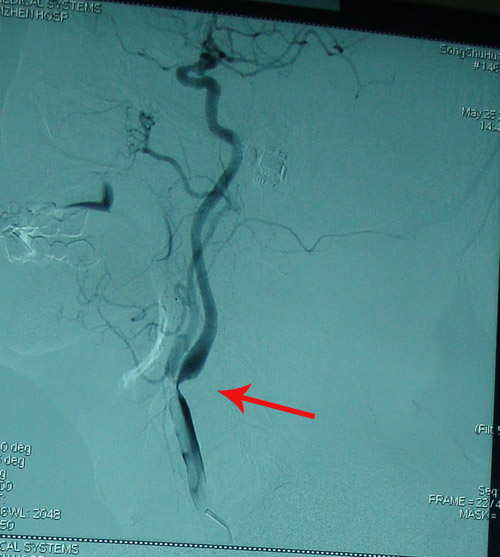

颈动脉椎动脉超声检查:左侧颈动脉血流通畅;右侧经总动脉分叉至颅内颈外动脉起始处狭窄;双侧椎动脉血流正向65-

右颈动脉狭窄